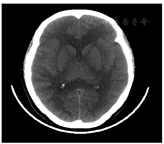

病例4 患者女,32岁,因"口服虫螨腈20 d,头痛头晕7 d,嗜睡1 d"于2020年11月26日18:05就诊。患者20 d前口服虫螨腈约5 ml(10%悬浮液),未诉不适,未行洗胃、导泻,当地诊所输液(具体药物不详)治疗1 d。7 d前出现头痛伴恶心、呕吐、多汗,到当地医院就诊,体温偏高(具体不详)、多汗,行颅脑MR示两侧脑组织大面积对称性斑片状肿胀,小脑扁桃体下疝;予以脱水、营养脑细胞、抗病毒药物治疗,1 d前患者出现嗜睡转诊我院。入院体格检查:T 38.1℃,P 98次/min,R 20次/min,BP 128/90 mmHg,嗜睡,多汗,双侧瞳孔直径约3 mm,对光反射迟钝;心肺腹未见明显异常,四肢肌4级,双侧Babinski征(-)。入院辅助检查:脑电图示广泛轻度异常,血常规、凝血常规、心电图未见明显异常;生化常规:MYO 346 ng/ml,CK3 762 U/L,CKMB 57 U/L,LDH 266 U/L,余未见明显异常;血气分析(FiO2:37%):pH 7.35,PCO2 35.6 mmHg,PO2 86 mmHg,tHb 14.2 g/dl,Lac 2.1 mmol/L。给予吸氧、脱水降颅压等综合治疗,入院后症状逐渐加重,2020年11月27日3:00出现昏迷,体温40.1 ℃,给予药物及冰毯物理降温无效,于6:00出现呼吸浅快、血氧饱和度下降,给予气管插管呼吸机辅助通气,升压药维持BP,呼吸机支持下复查颅脑CT示两侧诸脑沟、裂及脑池变窄/消失,脑室系统明显变窄,提示脑组织弥漫性肿胀(图1)。2020年11月27日14:05体温高达41.8 ℃,双侧瞳孔散大固定,对光反射消失,BP下降,随后心跳停止,拒绝医院心肺复苏出院。